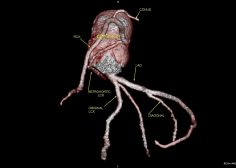

36Y male with chest pain, CT coronary shows a very rare anomaly. Twin LCX, (less than 10 cases in literature ).

The original LCX originates from LMCA , it supplies an early OM.

The 2nd anomalous LCX (arises from proximal RCA) with retro-aortic course till it reaches the left AV groove where it supplies a small OM.